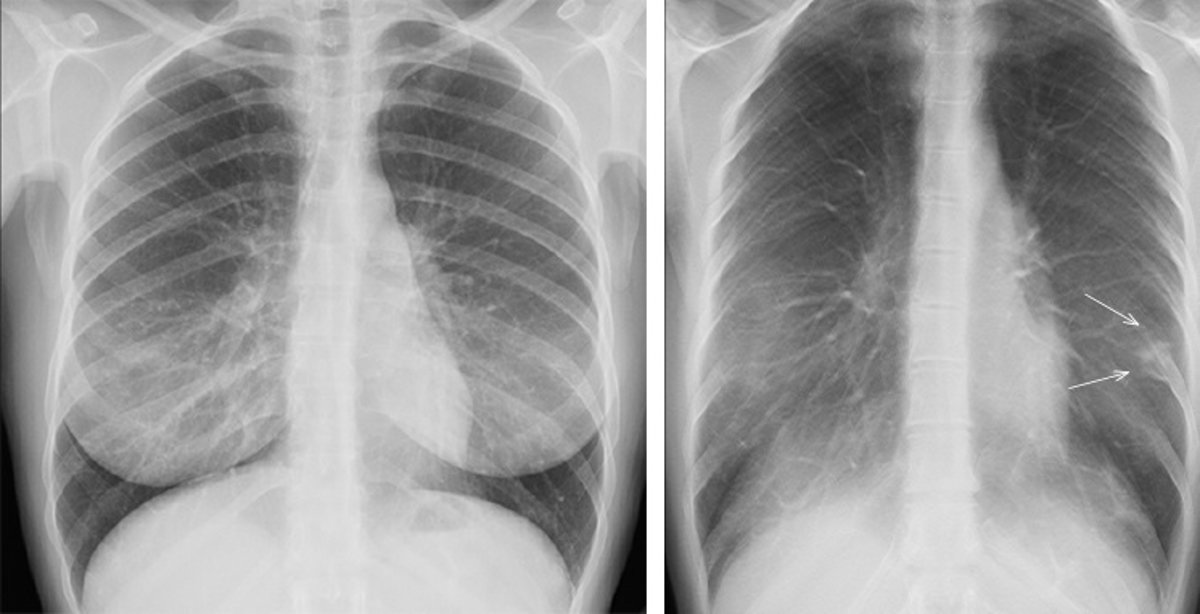

A la izquierda, una prueba de rayos X convencional. A la derecha, una imagen de un plano de tomosíntesis en la que se Identifica con claridad la patología que no se aprecia en la imagen de la izquierda.

A la izquierda, una prueba de rayos X convencional. A la derecha, una imagen de un plano de tomosíntesis en la que se Identifica con claridad la patología que no se aprecia en la imagen de la izquierda. - GE HEALTHCARE

En GE Healthcare recuerdan que, debido a la superposición de tejidos, es frecuente que en los primeros estadios de la enfermedad el radiólogo no vea la patología en una imagen digital convencional. Hasta ahora, la única manera de diagnosticar mejor estos pacientes era realizando una TC de tórax.

La tomosíntesis viene a mejorar el nivel de sensibilidad diagnóstica porque elimina el efecto de superposición de tejidos permitiendo la visualización con planos de alta resolución paralelos al plano del detector, según GE Healthcare. "Proporciona una localización tridimensional precisa y reduce la necesidad de exploraciones complementarias", añade.